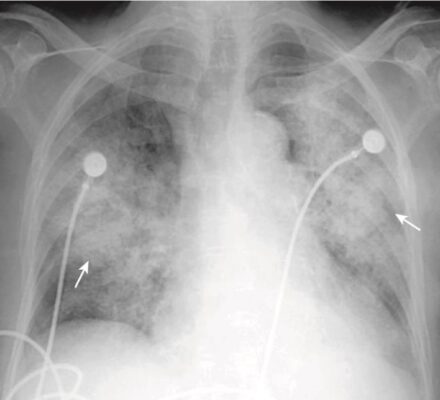

Phù phế nang phổi (Pulmonary alveolar edema)

- Phù phế nang phổi cấp tính điển hình thường tạo ra bệnh lý khoang chứa khí hai bên, quanh rốn phổi, đôi khi được mô tả là có hình dạng cánh dơi (bat-wing) hoặc cánh thiên thần (angel-wing) (Hình 6).

- Biểu hiện có thể không đối xứng nhưng thường không chỉ một bên. Phù phổi có nguồn gốc từ tim thường phối hợp với tràn dịch màng phổi và chất dịch làm dày các rãnh lớn và rãnh bé.

- Bởi vì chất dịch không chỉ lấp đầy các khoang chứa khí mà còn cả các phế quản, nên thường không có hình ảnh phế quản chứa khí trong phù phế nang phổi. Thường thì phù phổi hết nhanh sau khi điều trị (<48 giờ).